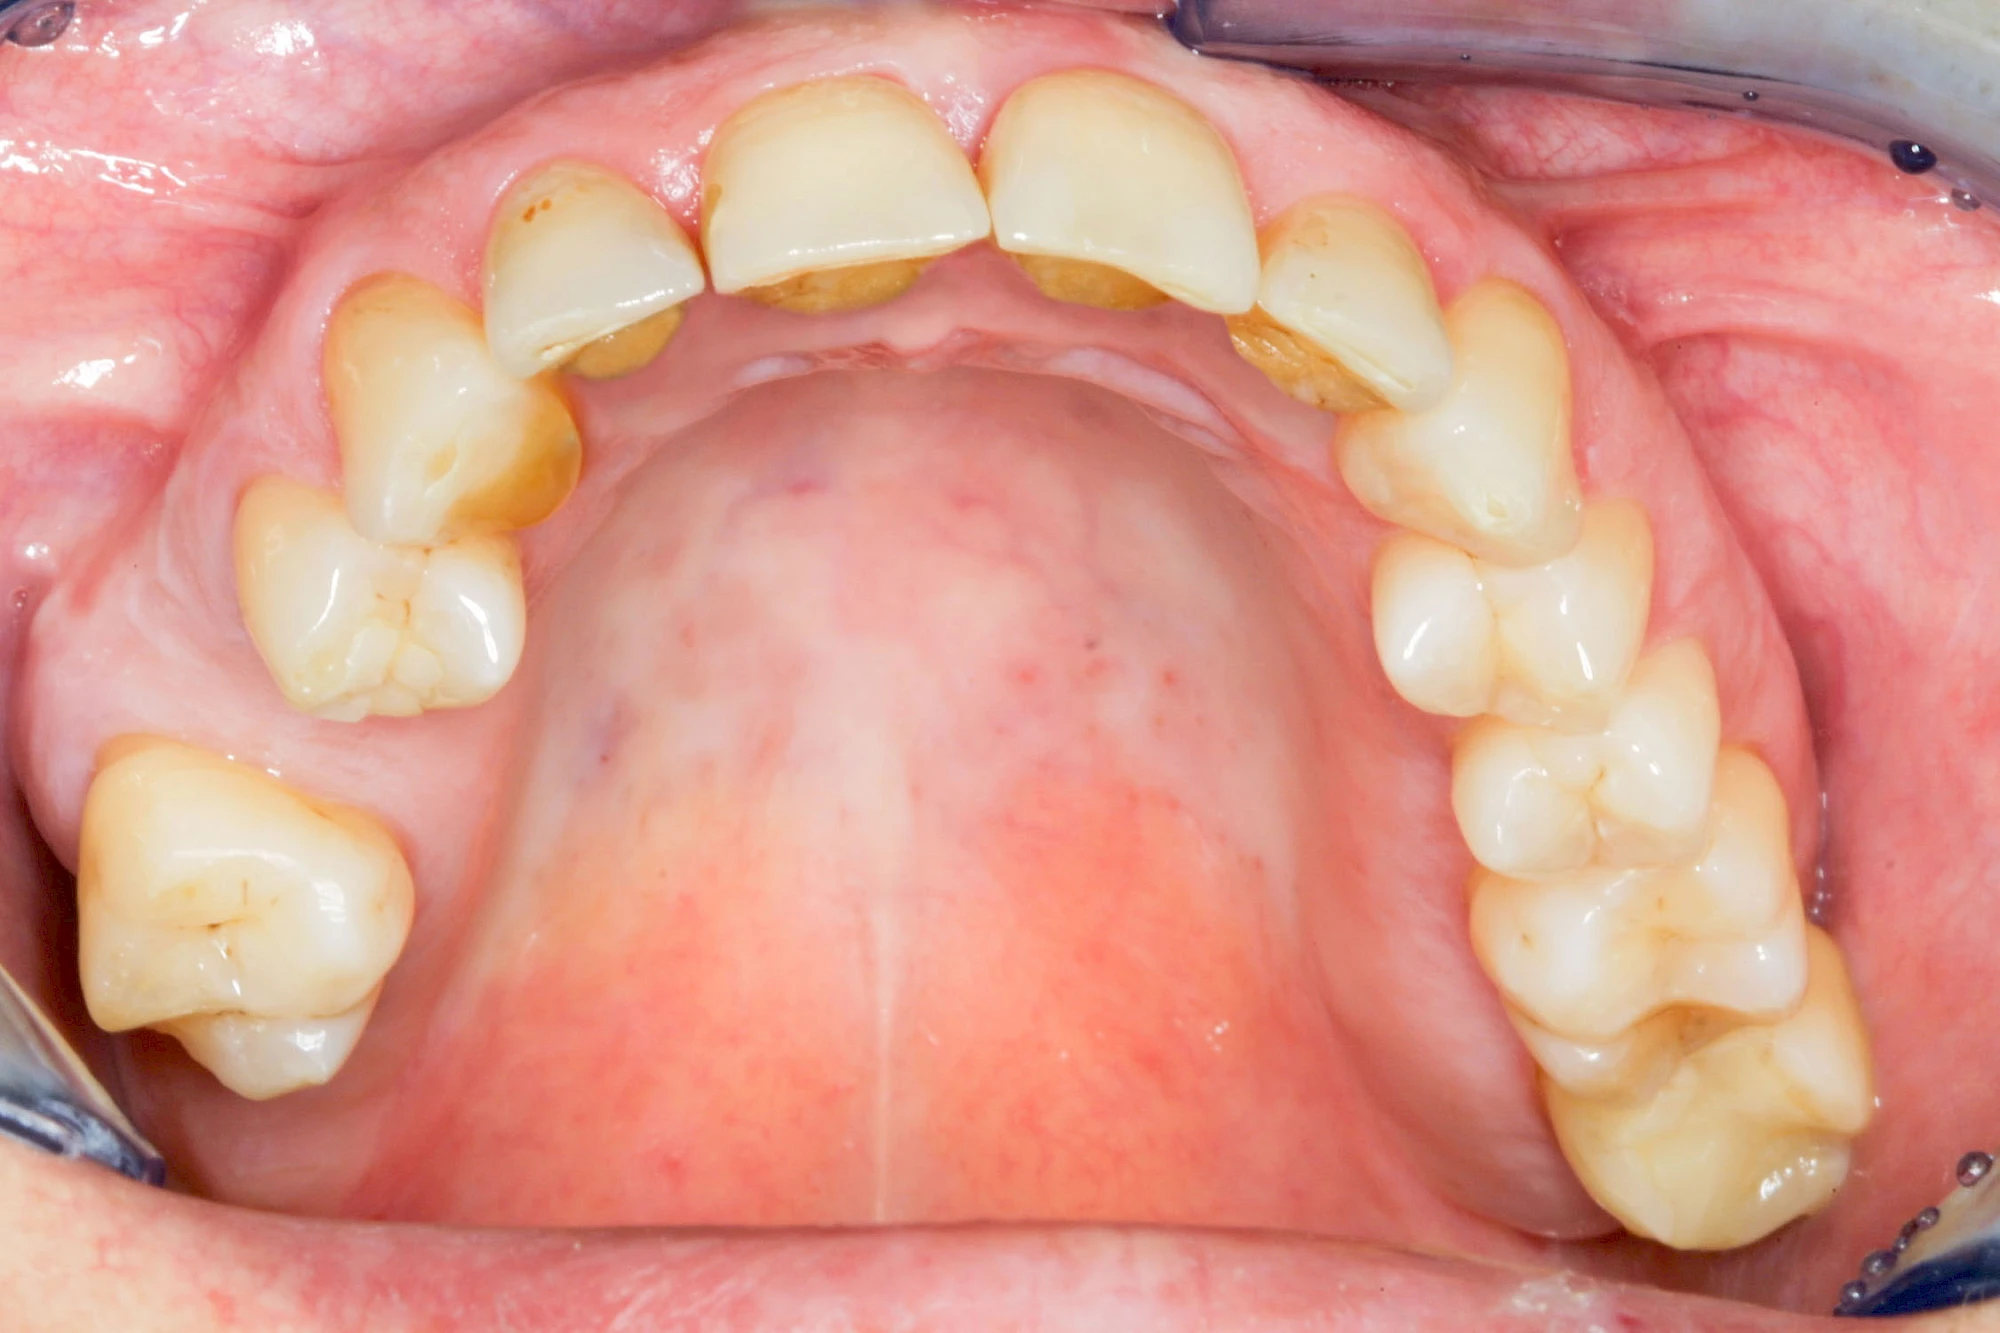

Implantate: Kronen & Brücken

Fehlen einzelne Zähne und die Nachbarzähne sind unbeschadet oder gut zahnärztlich versorgt, werden immer häufiger Implantate gewählt, um die Lücken zu schließen. Auch bei größeren oder verteilten Lücken, wenn keine herausnehmbare Prothese gewünscht ist, werden Implantate für Kronen- bzw. Brückenversorgungen gesetzt. In Einzelfällen entscheiden sich sogar zahnlose Patienten für eine festsitzende Versorgung auf Implantaten.

Varianten zur Verankerung von festsitzendem Zahnersatz auf Implantaten